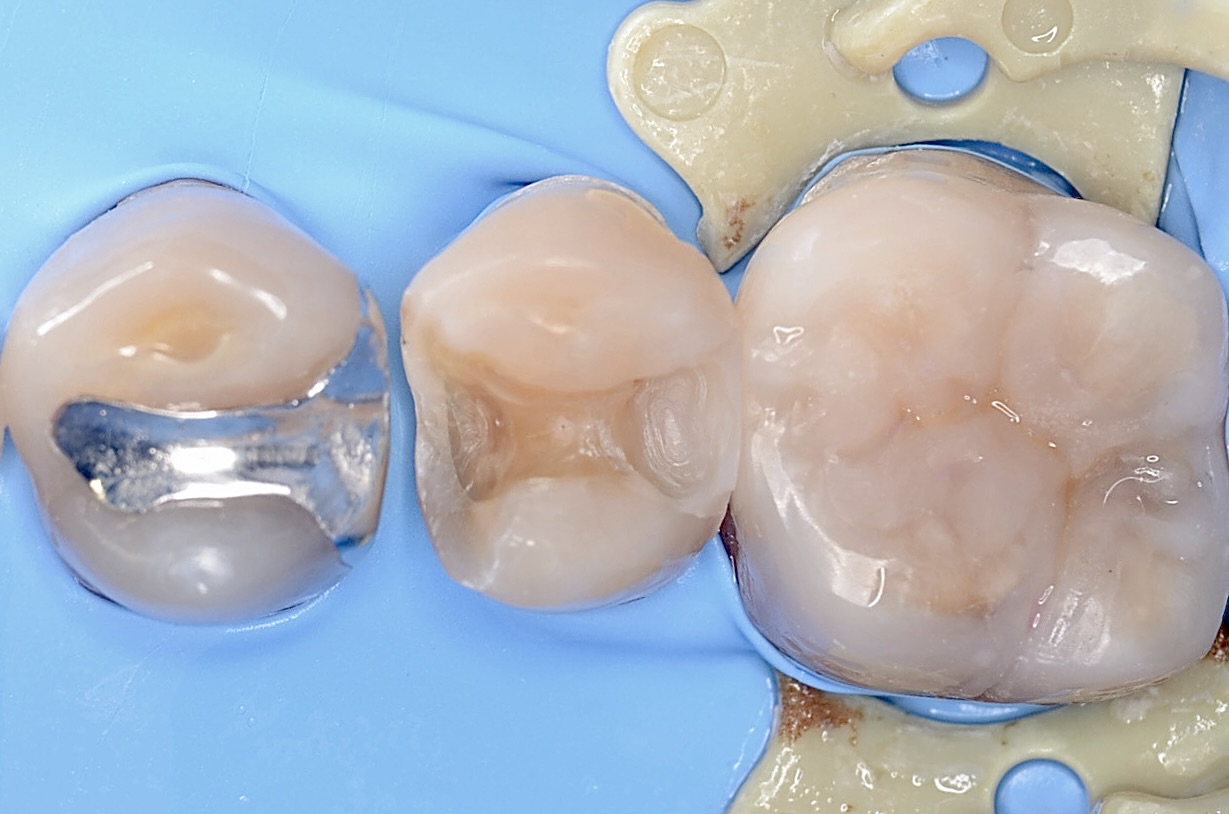

6番のインレーを除去

エナメル質のみを選択的に酸処理をして、接着力を増強させます。 -

6番ダイレクトボンディング

6番近心

6番の近親も虫歯でした。 -

6番近心ダイレクトボンディング

フロワブルレジンの表面張力を活かし滑らかに充填します。 -